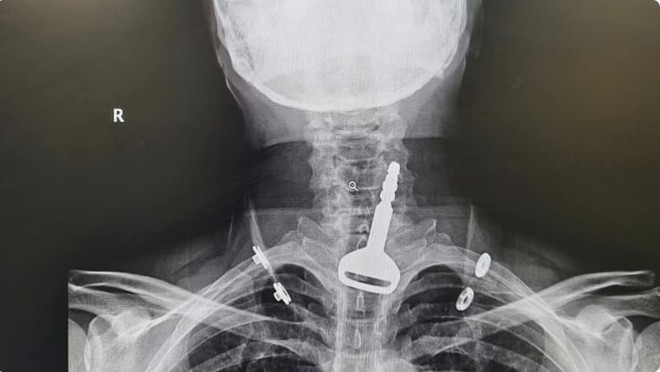

مریض کو سانس لینے میں انتہائی دشواری کا سامنا کرنا پڑرہا تھا(فوٹو، ٹوئٹر)

ہسپتال کے ہنگامی طبی امداد کے شعبے میں موجود ڈاکٹروں نے مریض کا فوری طورپرایکسرے کیا جس سے معلوم ہوا کہ اس کی سانس کی نالی میں گاڑی کی چابی پھنسی ہوئی ہے جس کی وجہ سے اسے سانس لینے میں شدید دشواری کا سامنا ہے۔

ڈاکٹروں نے فوری طورپراینڈواسکوپی کے ذریعے چابی کونکالنے کے لیے متعلقہ شعبے کو ہدایات جاری کردیں۔ مریض کو اپریشن روم میں منتقل کرکے سانس کی نالی میں پھنسی چابی کونکال لیا گیا جس سے اس کا نظام تنفس بحال ہوگیا۔

طبی کمیٹی کے نگران نے بتایا کہ اینڈواسکوپی کی ٹیم نے 15 منٹ کی جد و جہد کے بعد مریض کے حلق میں پھنسی چابی کونکال لیا۔ مذکورہ شخص چابی سے کھیل رہا تھا کہ چابی اچانک اس کے حلق میں پھنس گئی جس پراسے فوری طورپرہسپتال لایا گیا۔